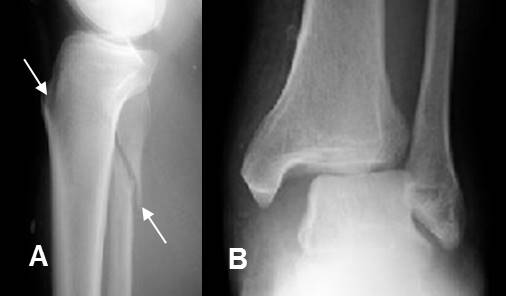

Fig 197. Fractura de Maisonneuve.

A: Rx lateral y B: Rx AP. Fractura espiroidea de la tibia y el peroné proximales, con diastasis de la mortaja tibio-peronea-astragalina, por lesión ligamentaria.